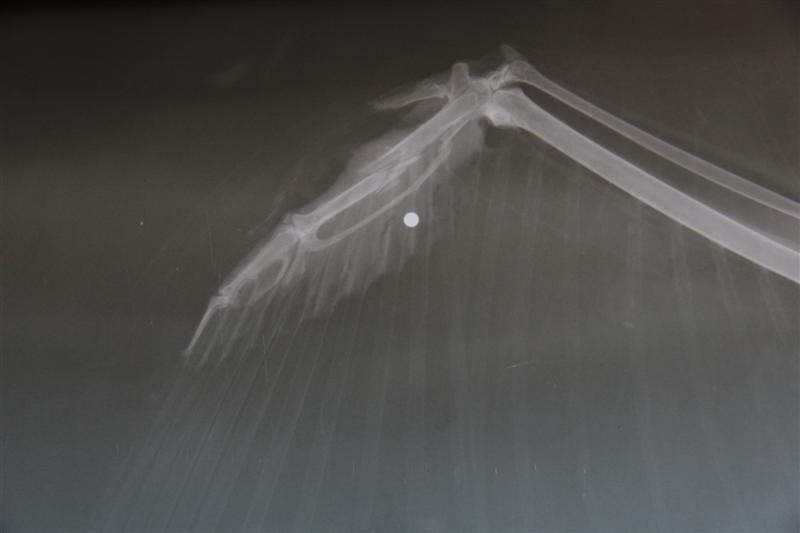

Alweer werd een geschoten buizerd opgevangen!

Afgelopen weekend kregen we weer een geschoten buizerd binnen. De vogel werd gevonden in Kaulille en had een gebroken vleugel en een gebroken poot ten gevolge van hagelinslag. Uiteraard

Operatie geschoten buizerd...

De buizerd die vorige week donderdag werd binnengebracht, onderging vandaag een operatie.

Verleden week berichtten we op deze website over een buizerd die gevonden werd in Sint-Truiden. Het dier had een vleugelbreuk, en na verdere

Buizerd door hagel getroffen...

Het is herfst en het jachtseizoen is weer volop aan de gang. Geregeld krijgen we telefoontjes van mensen met klachten over jagers. Die houden zich immers niet altijd braaf aan de regels...

dat werd vandaag ook weer eens bewezen. In Sint-Truiden werd